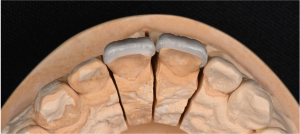

※ラミネートベニア咬合面

歯の表側と、歯の先端の一部が覆われていることがわかります。

※ラミネートベニア(口蓋側からみた状態)

ラミネートベニアは、通常、歯の内側は削らずに治療を行うため、歯を削る量を抑えることができます。